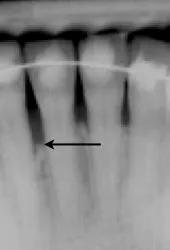

Periodontal Regeneration Case Studies Performed by Dr. Orth

Case 1: Before and after Periodontal Regeneration